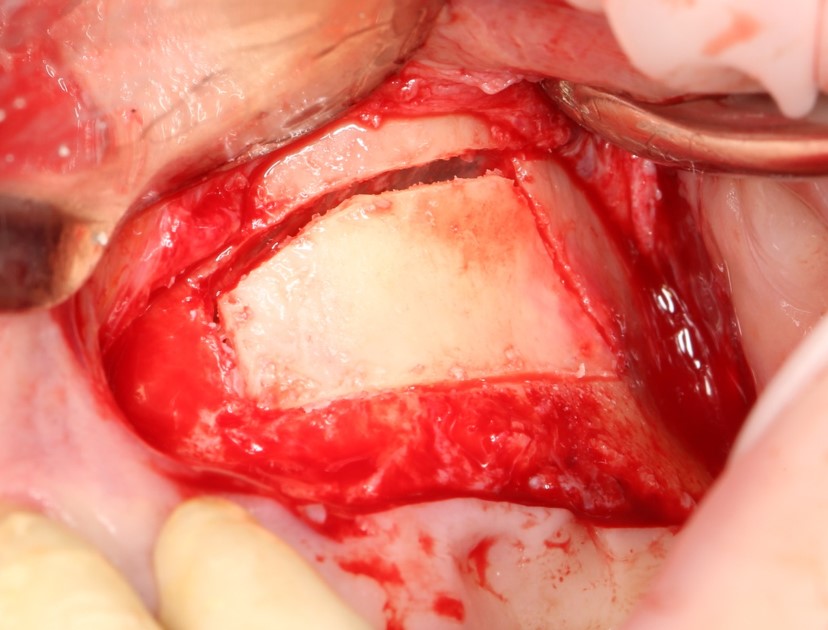

Кстати, обрати внимание на ширину альвеолярного гребня (левая картинка). Она чуть меньше 3 мм. Это объясняет, почему я засомневался в возможности установки имплантатов одновременно с остеопластикой. Понятно и без КЛКТ.

Для получения костного блока, мы открываем донорскую зону, наружную косую линию нижней челюсти.

Получение костного аутотрансплантата.

Здесь потребуется пародонтологический зонд с миллиметровой разметкой или какой-то другой измерительный прибор (операционная линейка). Ранее по КЛКТ я измерил костный дефект, теперь нужно нанести границы будущего костного блока на донорскую зону.

Ремарка: некоторые доктора предлагают делать хирургические шаблоны или выкройки специально для точного забора костного блока. На мой взгляд, это чрезмерное усложнение - во-первых, использование подобных шаблонов или выкроек требует увеличения площади раны, во-вторых, это увеличивает время и стоимость лечения, в-третьих, на этом этапе не требуется высокая точность, поскольку блок всё равно потребует адаптации.

Иными словами, важна не точность, а быстрый, аккуратный и, что главное, малотравматичный забор аутотрансплантата.

Для получения костного блока мы использовали ультразвуковую пьезохирургическую систему. Это самый удобный и безопасный инструмент для проведения подобных манипуляций. С помощью него мы сформировали и выделили костный блок. Он должен отделяться легким движением остеотома или элеватора. Как это сделать правильно — читай здесь>>